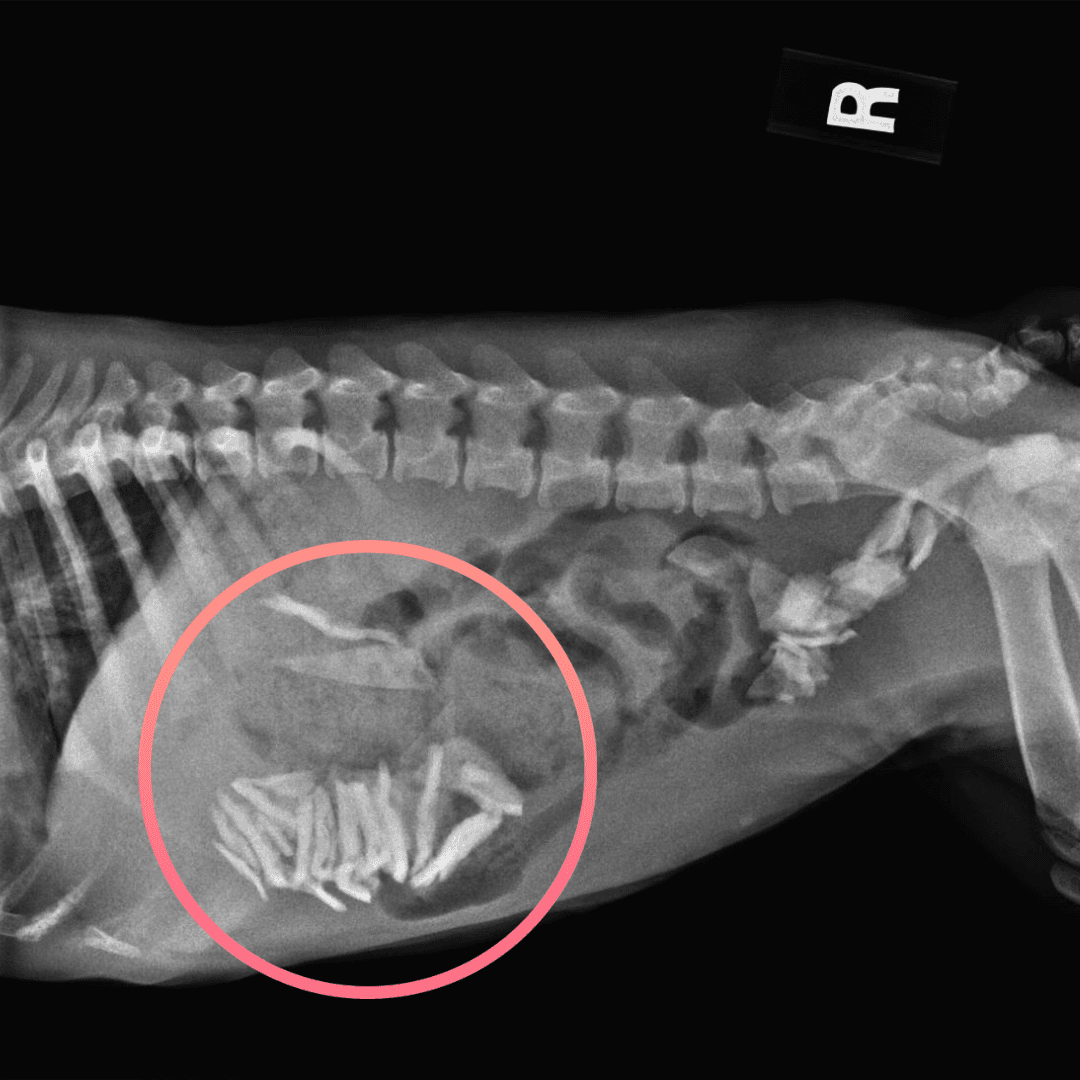

Her belly was full of glass.

Diamond had trouble walking due to orthopedic abnormalities, most likely due to irresponsible breeding, so went in for x-rays. What we found was shocking and heartbreaking. A belly FULL of glass shards needing immediate surgical intervention. These girls must have been scavenging for scraps and found themselves eating whatever they could find. Diamond will need to be monitored for the next two weeks - we are cautiously optimistic that there is no lasting damage to her organs. Diamond is on special medication to coat her GI tract to prevent further discomfort - we are all rooting for her!